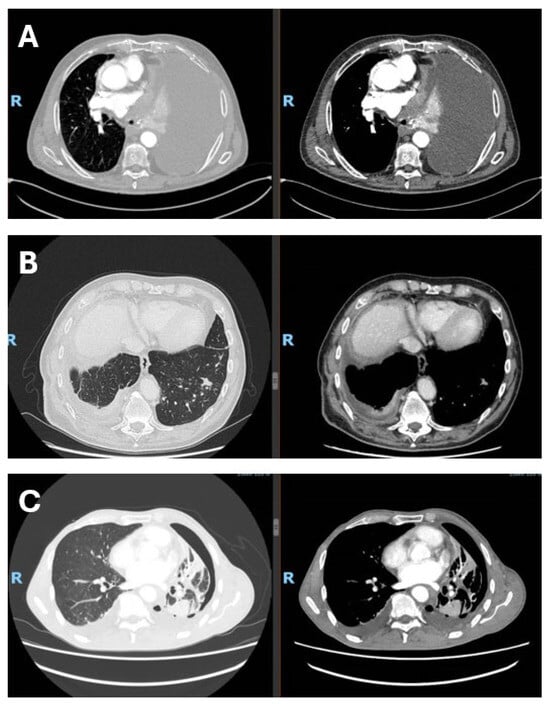

In this narrative review, we aim to summarize and critically discuss clinical trial data, real-world evidence, and emerging biomarker research on immune checkpoint inhibitors in malignant pleural mesothelioma. Malignant pleural mesothelioma (MPM) is a rare and highly aggressive tumor arising from the mesothelial cells of the pleura and is strongly associated with past asbestos exposure. Owing to its long latency—often exceeding two to three decades—MPM is frequently diagnosed at an advanced stage, when therapeutic options are limited and prognosis remains poor, with median survival generally ranging from 8 to 22 months. Despite asbestos bans in many countries, the global incidence of mesothelioma remains substantial, reflecting historical exposure patterns and the persistent use of asbestos in some regions, with more than 30,000 new cases estimated worldwide each year [1,2]. Asbestos fibers induce chronic inflammation, oxidative stress, and DNA damage within the pleural space, creating a pro-tumorigenic environment that ultimately promotes malignant transformation [3,4]. From a prognostic perspective, MPM remains associated with high mortality, with median overall survival generally below 18 months across population-based and multicenter cohorts, despite variability related to histology, stage, and systemic inflammatory status [5,6]. Real-world studies and national registry data consistently confirm the aggressive natural history of the disease, the heterogeneity of treatment pathways, and persistently limited outcomes despite recent therapeutic advances [7,8]. For many years, therapeutic options were largely confined to surgery, radiotherapy, and platinum–pemetrexed chemotherapy, with no substantial survival gains. Even aggressive multimodal strategies have failed to demonstrate meaningful benefit, as shown by the MARS 2 trial, which reported no improvement—and increased morbidity—with extended pleurectomy/decortication compared with chemotherapy alone [9]. Consequently, MPM remains an area of major unmet clinical need, with primary prevention through elimination of asbestos exposure still representing the most effective strategy. According to the 2021 World Health Organization (WHO) [10] classification of thoracic tumors, MPM includes the epithelioid, sarcomatoid, and biphasic subtypes, as well as preinvasive or low-grade entities such as mesothelioma in situ (MIS) and well-differentiated papillary mesothelial tumor (WDPMT). MIS is defined as a mesothelial proliferation confined to the pleural surface, morphologically similar to reactive processes but characterized by molecular alterations associated with neoplastic transformation. WDPMT is a rare lesion with low malignant potential, characterized by papillary proliferations of mesothelial cells without significant cytological atypia or the molecular alterations typical of malignant mesothelioma, and is associated with an indolent clinical course and favorable prognosis, although rare local recurrences may occur. Among invasive forms, epithelioid mesothelioma is the most frequent subtype and is associated with a relatively more favorable prognosis compared with sarcomatoid and biphasic variants. In this context, the WHO 2021 classification introduced a two-tier grading system (low/high grade) for epithelioid mesothelioma, based on nuclear atypia, mitotic activity, and necrosis, with relevant prognostic implications and the aim of improving interobserver reproducibility and standardizing routine histopathological reporting. Sarcomatoid mesothelioma is associated with the poorest prognosis, while biphasic mesothelioma shows an intermediate clinical behavior, strongly influenced by the proportion of the sarcomatoid component, the increase of which represents a negative prognostic factor [10]. Representative CT images from patients with malignant pleural mesothelioma are shown in Figure 1.

Figure 1.

Radiological presentation of malignant pleural mesothelioma subtypes. (A) Epithelioid subtype with massive pleural effusion at presentation; (B) sarcomtoid subtype with infiltration of the visceral pleura and diaphragm, associated with contralateral metastasis; (C) biphasic subtype with visceral pleural involvement and trapped lung. The figure was created by the authors and does not include material subject to copyright.